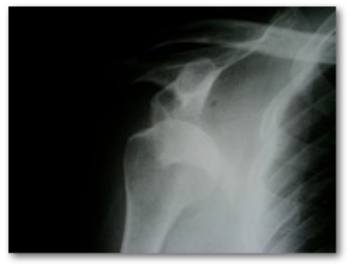

Hombro luxado, nota como esta fuera de lugar